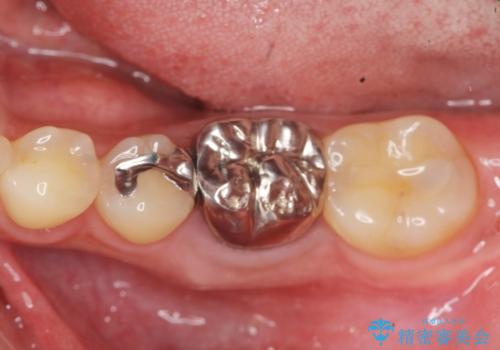

抜歯後ブリッジとインプラント治療を検討・相談し、より周囲の歯を削らずに済むインプラント治療を希望されたのでインプラントによる機能回復を計画します。

- 46.2万円(インプラント・チタンカスタムアバットメント・仮歯・ジルコニアクラウン)費用は治療当時の料金となります